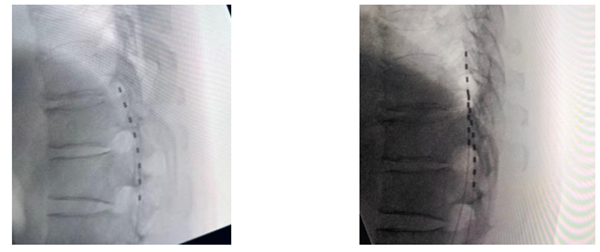

患者金先生,62岁,多年来深受偏瘫困扰,2017年因高血压脑出血,术后遗留左侧肢体偏瘫:上肢无法完成抓握、对掌动作,下肢伴随剧烈疼痛与肌肉僵硬,行走呈“划圈步态”,夜间常因剧痛难眠。为重建上肢功能,胡主任于2025年为其实施颈七神经移植术,通过将健侧颈七神经根精准移位至患侧,重建神经传导通路。术后经系统康复,金先生患肢功能较前好转,曲肘,伸腕目前已实现对掌功能,可自主持物、搭积木等,生活自理能力大幅提升。但下肢痛痉仍严重影响生活质量,传统治疗效果不佳。胡主任评估后,决定启用科室新业务——脊髓电刺激术(SCS)。该技术是神经调控领域前沿手段,通过微创手术将电极植入脊髓硬膜外腔,释放温和电脉冲,阻断疼痛信号传递、降低肌张力,且微创可逆、可动态调节参数。手术由胡叶帅主任带领团队分两期完成:一期在影像引导与术中电生理监测下精准植入电极,临时刺激验证效果;二期植入永久脉冲发生器。“开机瞬间,疼痛感就消失了,肌肉也放松了。”金先生术后下肢肌张力显著降低,行走更协调,夜间睡眠恢复正常。